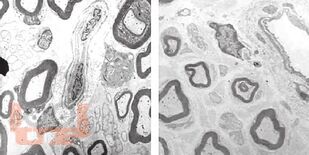

Возрастной андрогенный дефицит у мужчин

Возрастной андрогенный дефицит, несмотря на высокую распространенность, изучен недостаточно полно. Актуальность проблемы связана с тем, что дефицит андрогенов проявляется не только нарушением половой функции, но и ассоциирован со многими возрастными заболеваниями (ожирение, сахарный диабет, ИБС, остеопороз и др.), ухудшая их течение и прогноз.